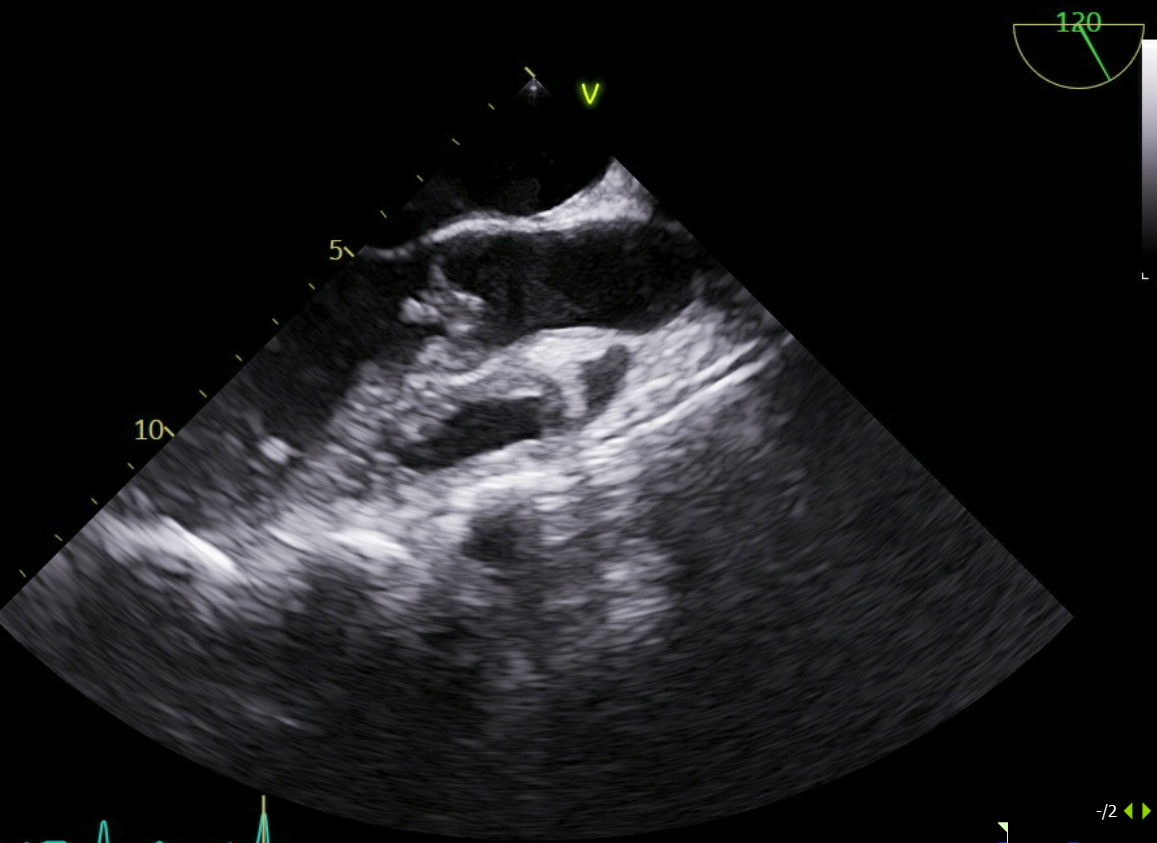

Transthoracic echocardiography (TTE) showed an ejection fraction of 58% with a mobile echodensity on the aortic valve, severe aortic regurgitation, and holo-diastolic flow reversal in the descending aorta. Transesophageal echocardiography (TEE) confirmed a 1.4 × 0.8 cm mobile echogenic mass consistent with vegetation, and an abscess in the right coronary part of the aortic annulus. The patient was started on broad-spectrum antibiotics, including vancomycin and ampicillin-sulbactam.